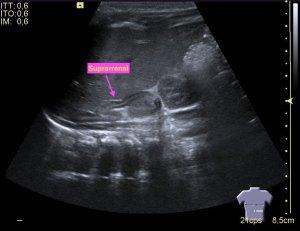

La vesícula biliar es un órgano en forma de pera que se encuentra debajo del hígado, en hipocondrio derecho.

Tiene un cuello que se conecta con el conducto cístico y un cuerpo que se compone de tres partes, cuello, cuerpo y fundus.

- Vesícula biliar: Visualizada como una estructura en forma de pera, que puede variar en tamaño según la cantidad de bilis que contenga. Su pared aparece como una línea hiperecogénica y suele tener un grosor menor a 3 mm.